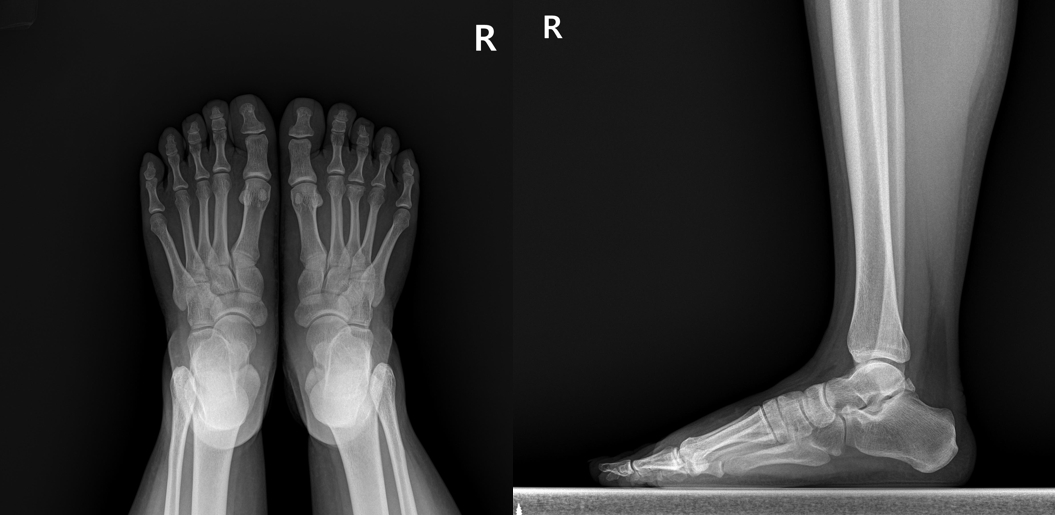

박상준 의원 병원위치, 진료시간, 연락처 등등이 궁금하면 클릭하세요. ^^ (당산 정형외과 당산역 정형외과 당산동 정형외과 여의도 합정 목동 영등포 영등포구청 선유도 양평동 국회의사당 정형외과 야간진료 도수치료 통증의학과 박상준의원) 안녕하세요 당산 정형외과 박상준의원 대표원장 박상준입니다. 오늘은 발등이 괜히(?) 아프다고 온 여자 이야기를 해볼까 합니다. 얼마전에 젊은 여성분 한분이 진료실에 들어오셨습니다. 나 : 어디가 아파서 오셨어요? 여성 : 발이 아파요 ㅜㅜ 나 : 언제부터 아프셨어요? 다치셨어요? 여성 : 대략... 3주정도 되었어요. 다친적은 없구요. 나 : 병원에는 처음오셨나요? 여성 : 다른데 가서 x-ray 한번 찍고 물리치료 받았는데 계속 아프네요,, ㅜㅜ 몇주전부터 발등이 아프다는..